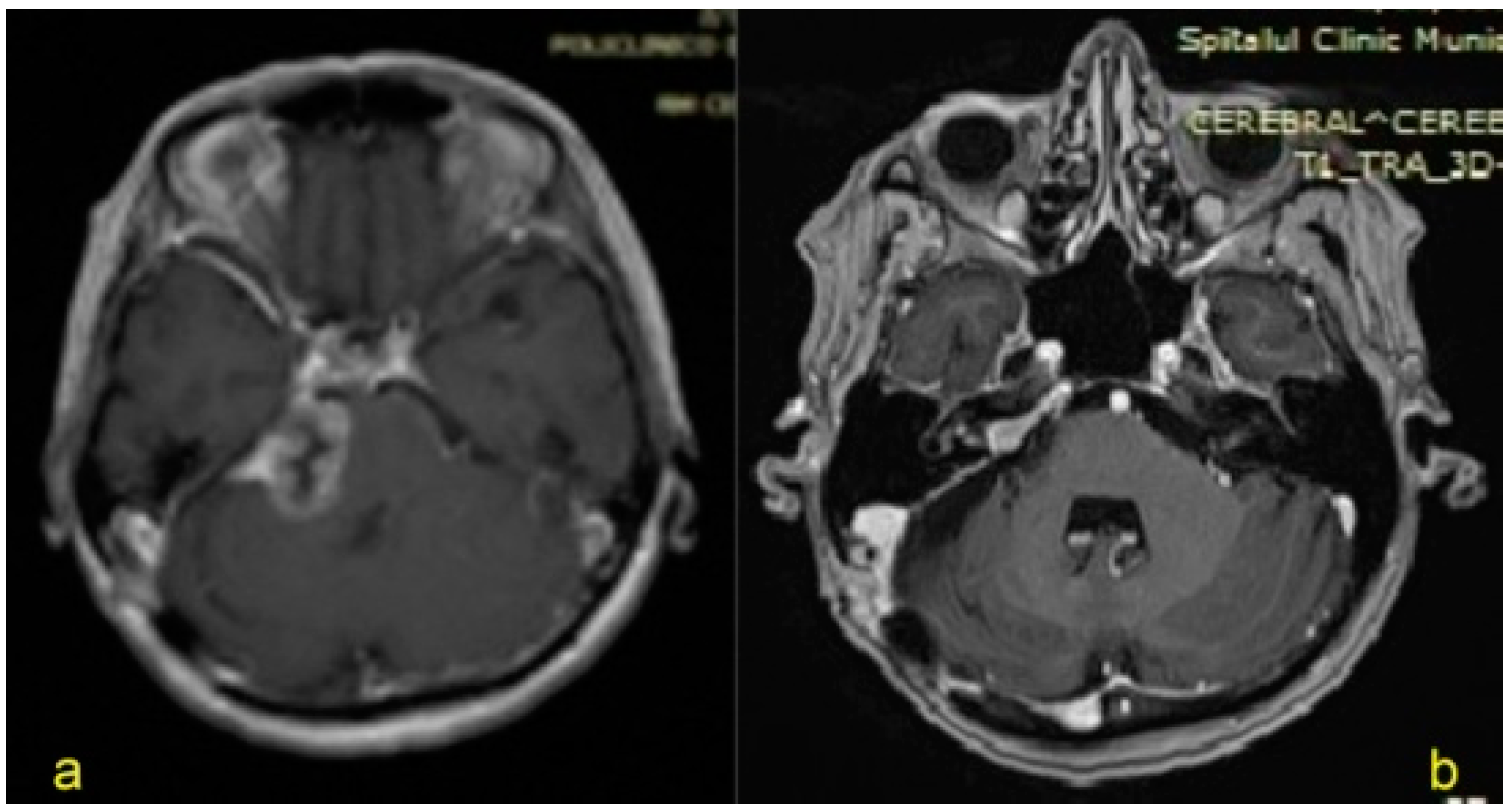

| 1. | 61/F | VS (Jun 2015) Koos grade IV(large tumor with brainstem displacement) | Breast cancer(treated surgically in 2013), CIPN—TNSc grade 2 | 19 | Tarsorrhaphy | VI/III (right side) Total paralysis/obvious weakness but not totally disfiguring, complete eye closure with effort and symmetric at rest | - |

| 2. | 65/F | VS (Sep 2016) Koos grade IV | Uterine cancer, Melanoma (treated surgically in 2014), CIPN—TNSc grade 2 | 13 | Tarsorrhaphy | VI/III (right side) | - |

| 3. | 64/M | VS (Apr 2015) Koos grade IV | - | 26 | Tarsorrhaphy | VI/IV (left side) Total paralysis/Disfiguring weakness, incomplete eye closure and asymmetric at rest | CSF leak Hydrocephalus (VCS, right VP shunt) |

| 4. | 63/F | VS (Jan 2018) Koos grade IV | Chronic hypothyroidism (2006) PN—TNSc grade 2 | 6 | Tarsorrhaphy | VI/IV (left side) | - |